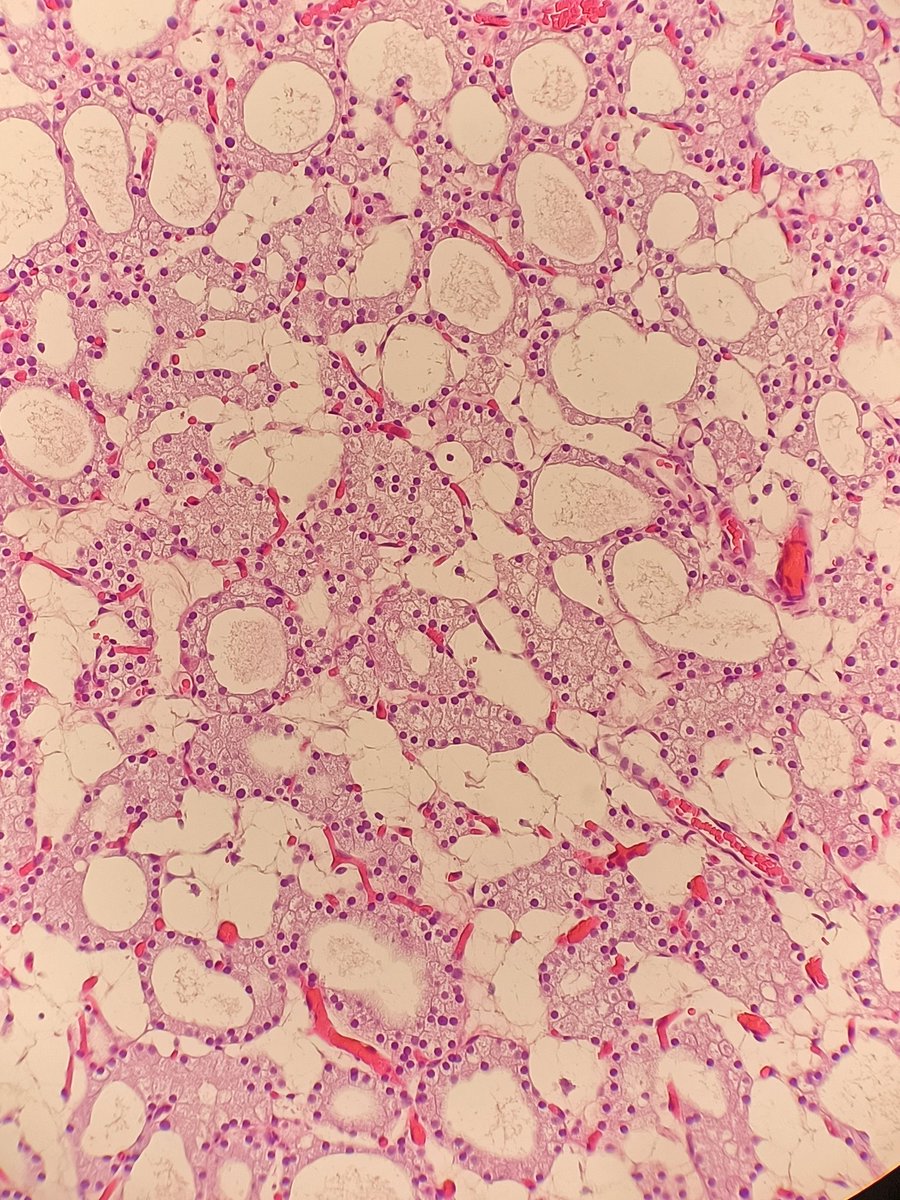

Here's an uncommon entity in #HeadandNeckPath. A cute 💧💧💧water-clear cell parathyroid adenoma 💧💧💧. The name says it all! Some areas have cystic changes too. #ENTPath